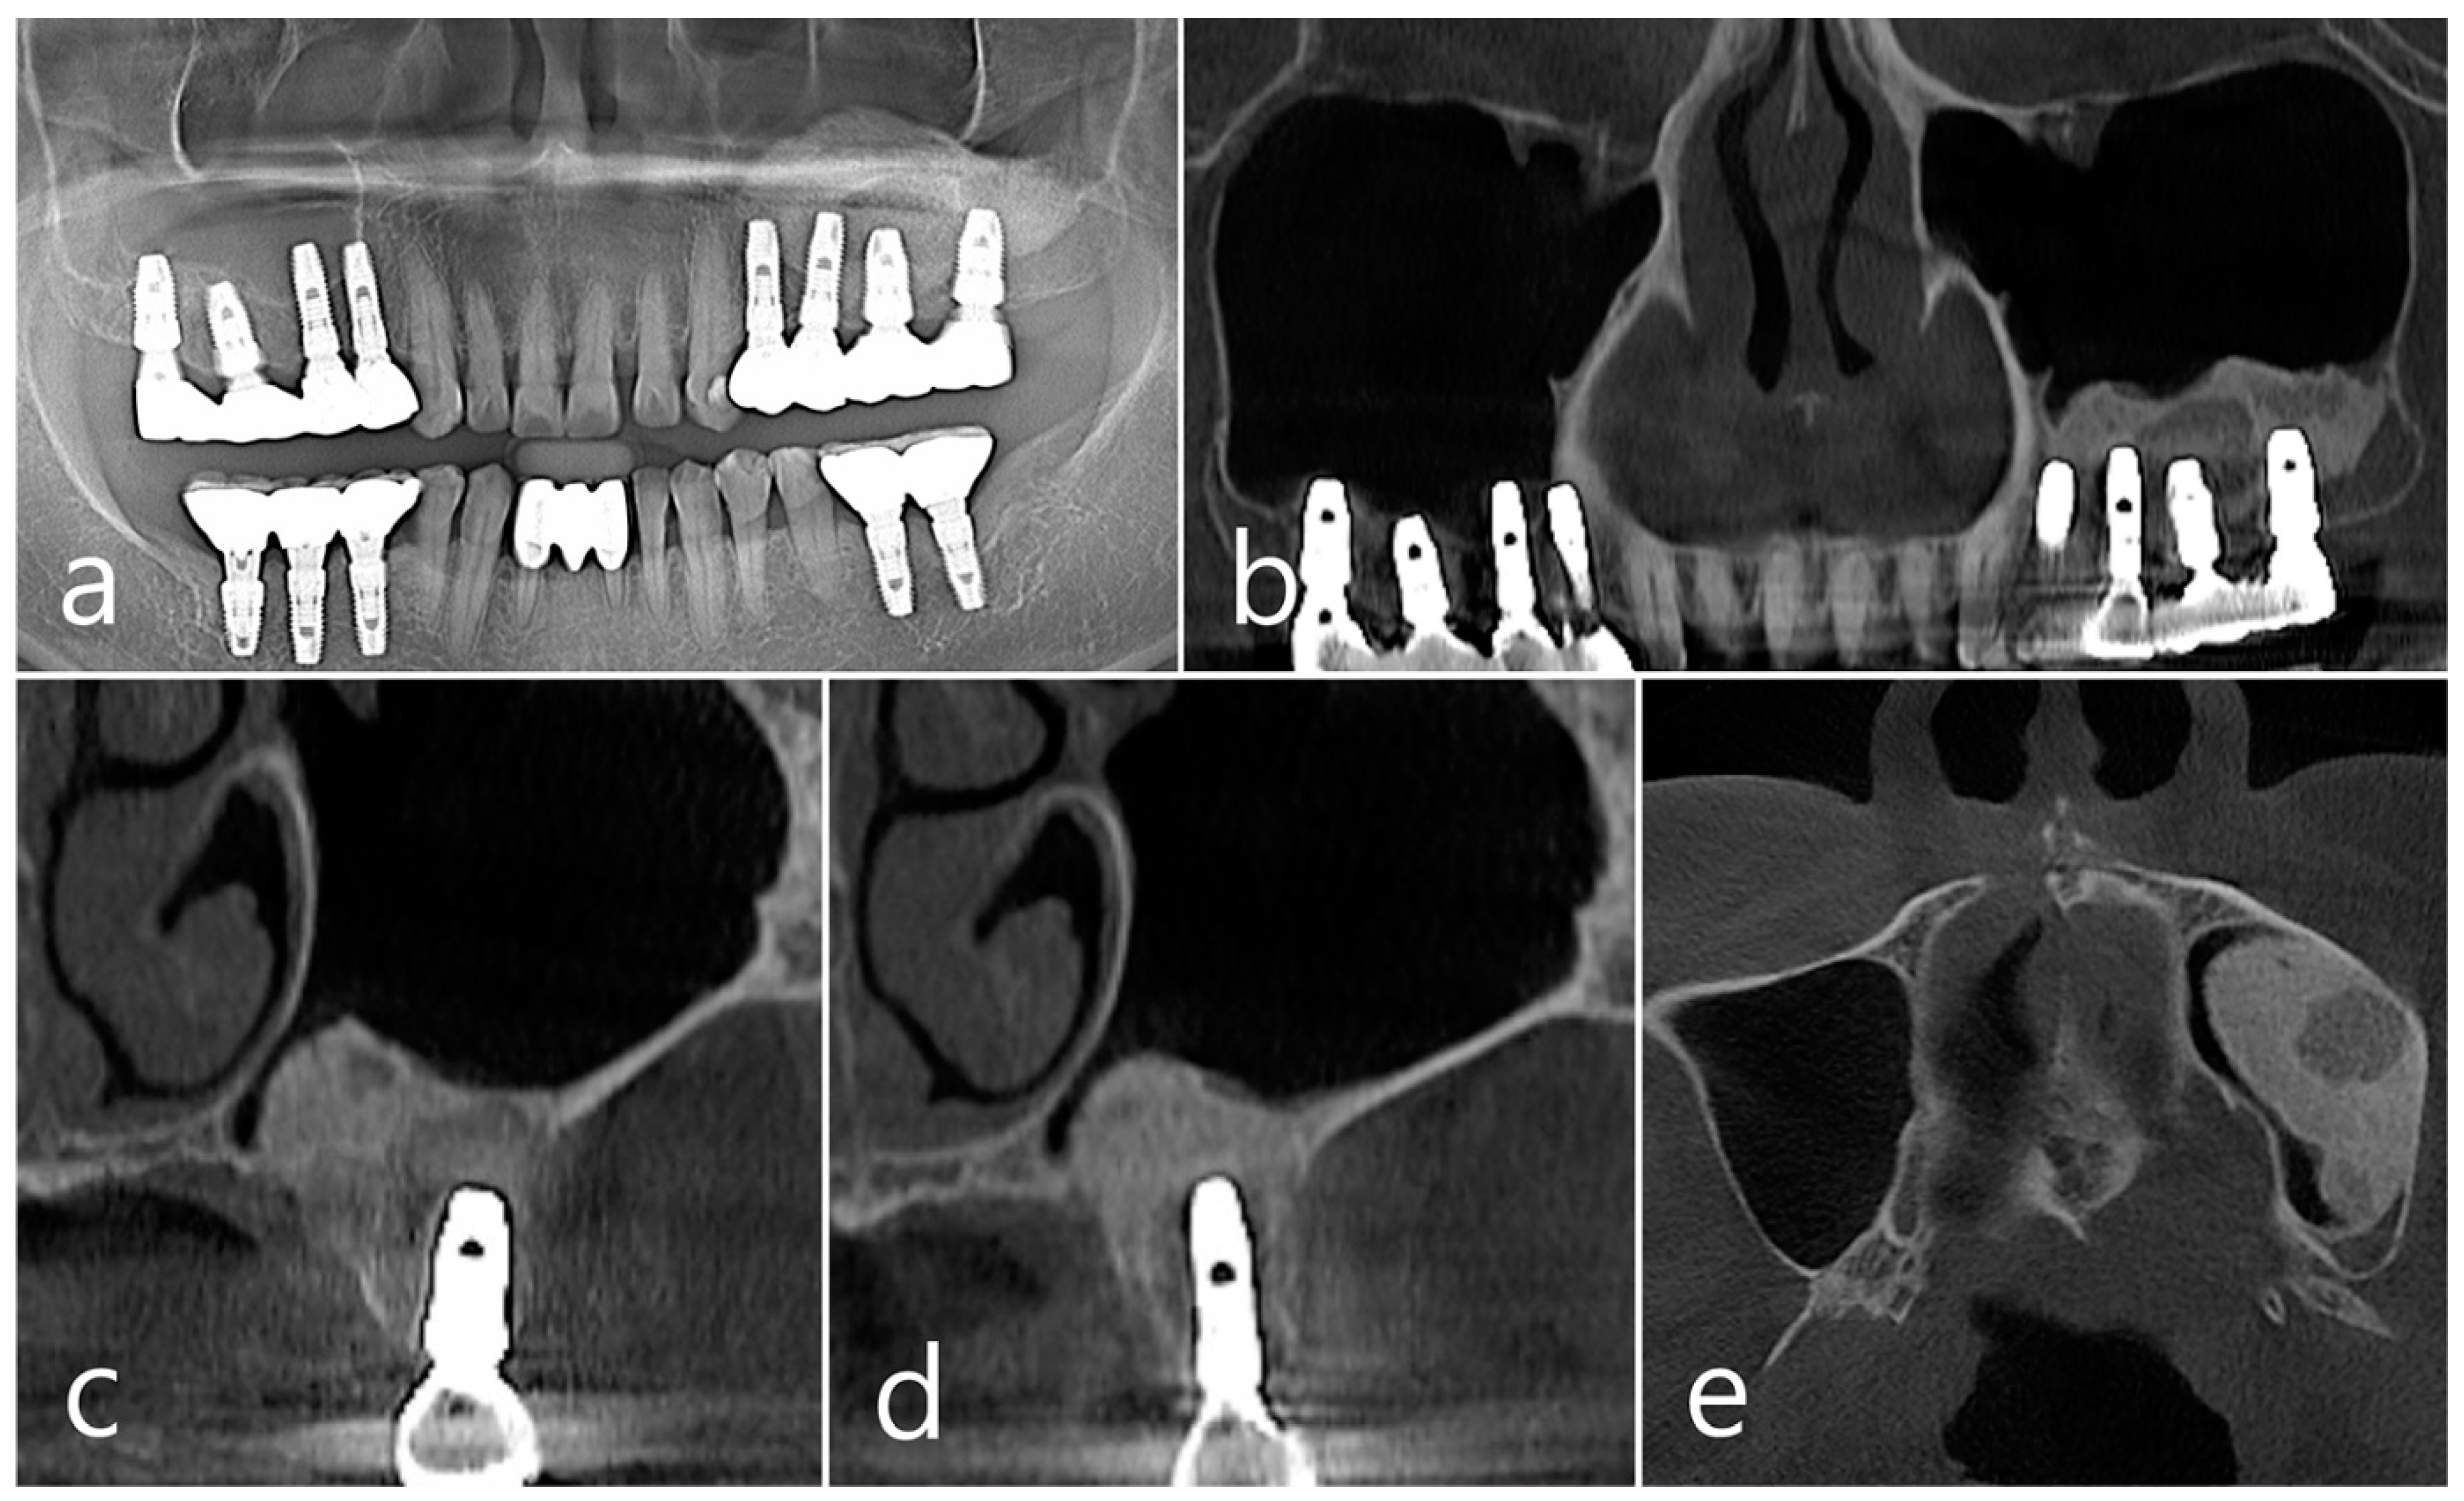

In the CBCT image taken immediately after the procedure, a well-filled bone graft substitute without perforation of the sinus membrane was observed (Figure 8d–f). However, extensive bone loss was found in CBCT images taken 2 years after the prosthesis was placed. The facial cortical bone plate was lost, and bone resorption was present only within the sinus graft. The appearance of the sinus graft was not invaded, and the thickness of the sinus mucosa was normal (Figure 8g–i).

Surgical intervention was decided after the prosthesis was retrieved (Figure 9a). Under local anesthesia, the buccal mucoperiosteal flap was reflected. A severe bone defect was observed in the sinus bone graft of the #26 implant. Thorough debridement was performed on the bone defect in the maxillary sinus bone graft. There was no difficulty in removing the inflammatory granulation tissue because it bordered the surrounding healthy bone graft (Figure 9b). The exposed implant achieved osseointegration, but the large implant surface was exposed and contaminated. Mechanical decontamination was thoroughly performed using a titanium brush and titanium curette, and additional detoxification with tetracycline HCl was performed (Figure 9c). After sufficient saline irrigation again, a bone graft (Osteon II, Genoss, Suwon, Republic of Korea) was performed (Figure 9d). The bone graft area was covered with a resorbable collagen membrane (Genoss, Suwon, Republic of Korea) (Figure 9e). The mucoperiosteal flap was closed with 4-0 nylon. Healing was uneventful, and the prosthesis was re-inserted again 1 month after GBR. The specimen was fixed in 10% formalin for histopathological examination. In the specimen, granulation tissue infiltrated with inflammatory cells, and necrotic bone graft particles were observed (Figure 9f). The patient was followed up once every 6 months, and panoramic radiography and CBCT were taken 2 years after GBR (Figure 10a,b). The bony defect was filled with bone tissue, and no abnormal radiographic images were observed. Corticalization of the buccal bone was well achieved (Figure 10c,d).

Figure 8. (a) Teeth #24 and #25 were extracted, midcrestal and vertical incisions were performed, and mucoperiosteal flaps were reflected; (b,c) A lateral sinus window was prepared, and sinus floor elevation was performed without membrane perforation. The bone graft substitute was delivered and covered with a resorbable collagen membrane. The flap was closed; (df) In the CBCT image taken immediately after the procedure, a well-filled bone graft substitute without displacement was observed; (gi) Extensive bone resorption around #26 implant was observed in CBCT images taken 2 years after prosthesis delivery. The buccal cortical bone plate was lost, and bone resorption was present only within the sinus graft.